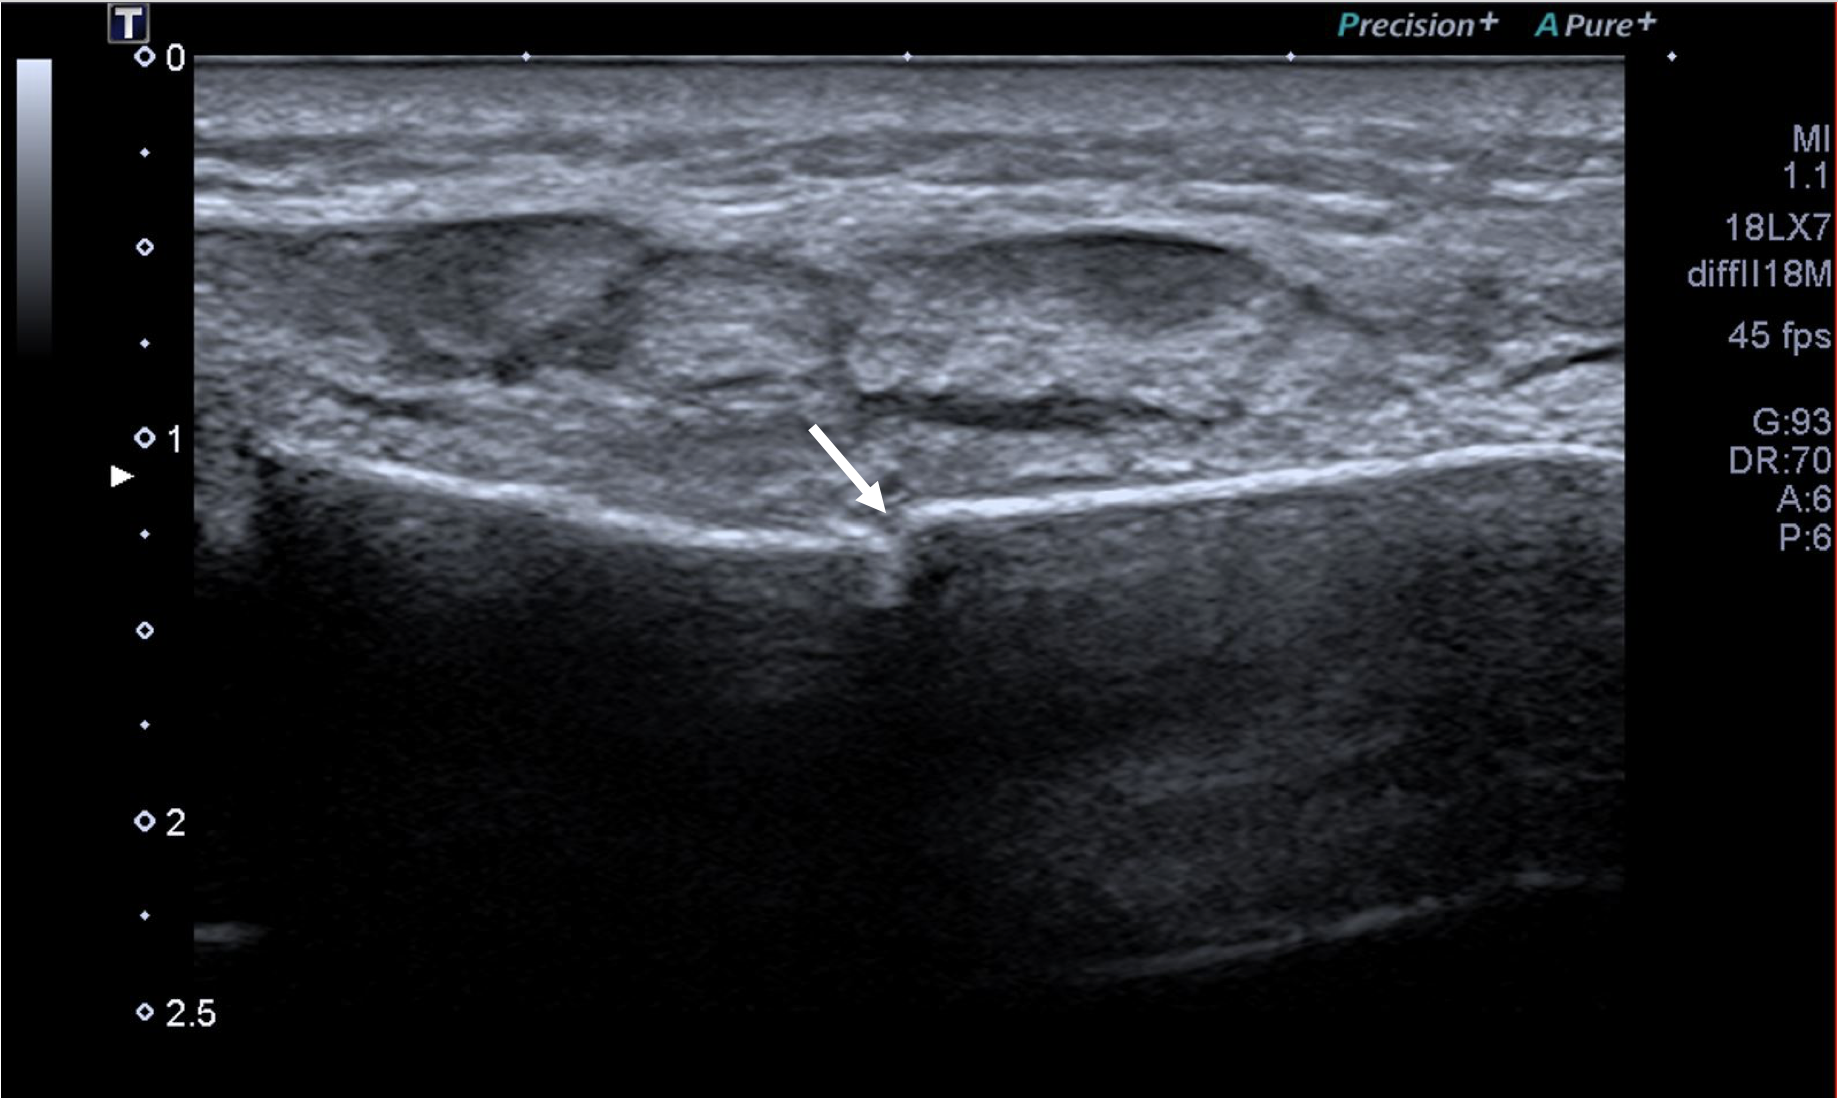

An ultrasound examination of the chest performed using a Toshiba Aplio 500 high-frequency probe showed an acute linear fracture through the anterior cortex of the sternum just below the level of the sternomanubrial joint (FIGURE 1). The subjacent third costal cartilage was unremarkable. A bone densitometry DEXA scan showed osteoporosis of the L2-L4 vertebral bodies with both T-score and Z-scores measuring -2.9 (FIGURE 2). Bone density of the bilateral femora was normal (T score -0.9). Further imaging of the neck was arranged to investigate the cause of the inappropriate parathyroid hormone levels. An ultrasound of the neck revealed a well-defined, hypoechoic nodule located just inferior to the lower pole of the left lobe of the thyroid gland measuring 14x8x5mm (FIGURE 3). The patient then underwent a SPECT-CT of the neck and chest to ensure co-localisation on two imaging modalities. 739 MBq of technetium 99m was injected and acquisitions were obtained at 10min, 90mins and 180mins following tracer injection. Analysis of the SPECT data demonstrated a well-defined area of retained activity situated in the lower pole of the left lobe of the thyroid which correlated well with the findings of the ultrasound scan (FIGURE 4). The overall appearances were in keeping with a parathyroid adenoma situated in the lower pole of the left lobe of the thyroid. The CT component of the study also showed a further view of the fracture (FIGURE 5).